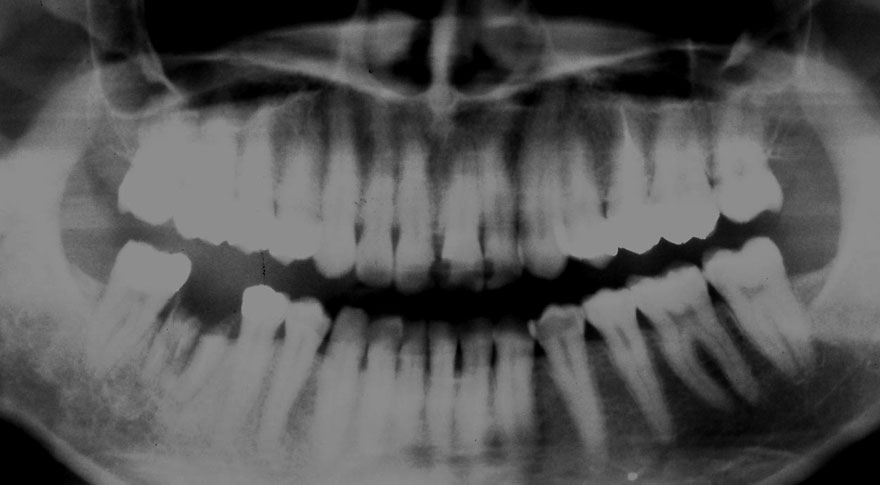

初診時 19歳 女性

虫歯多発傾向

31年後 50歳